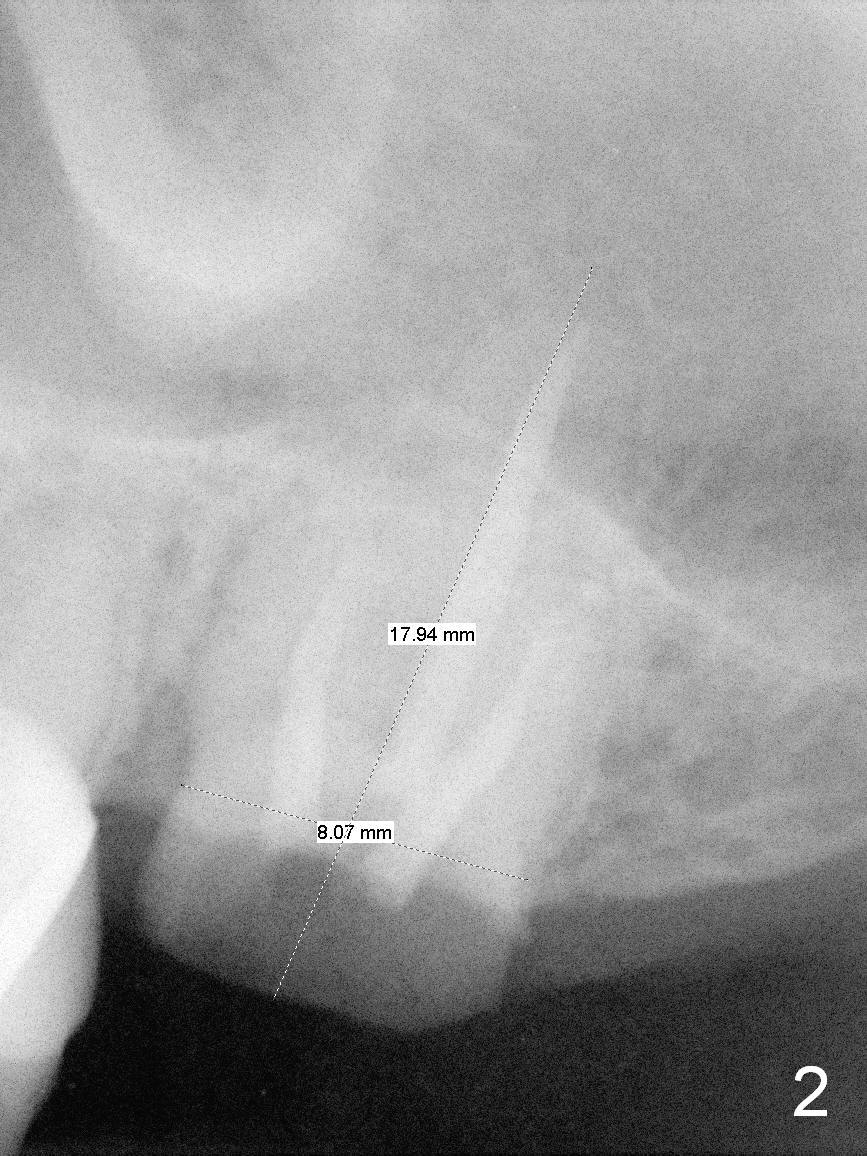

PA shows that the depth of the osteotomy is approximately 17 mm (Fig.2), whereas CT 14 mm (Fig.3,4). Intraop measurement will determine the depth.